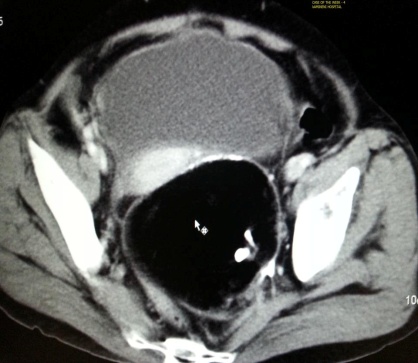

Ovarian cystic teratoma contains mature epithelial elements such as sebum, hair, epithelium, calcium, desquamated skin, and other elements which give complex appearance. Although they do not contain fat, they contain sebum which is lipid material with characteristic signal similar to fat. This differentiates it from other masses (Figures 11, 12, 13ab & 14).

Figure 13a,b: Germ cell tumour of ovary.